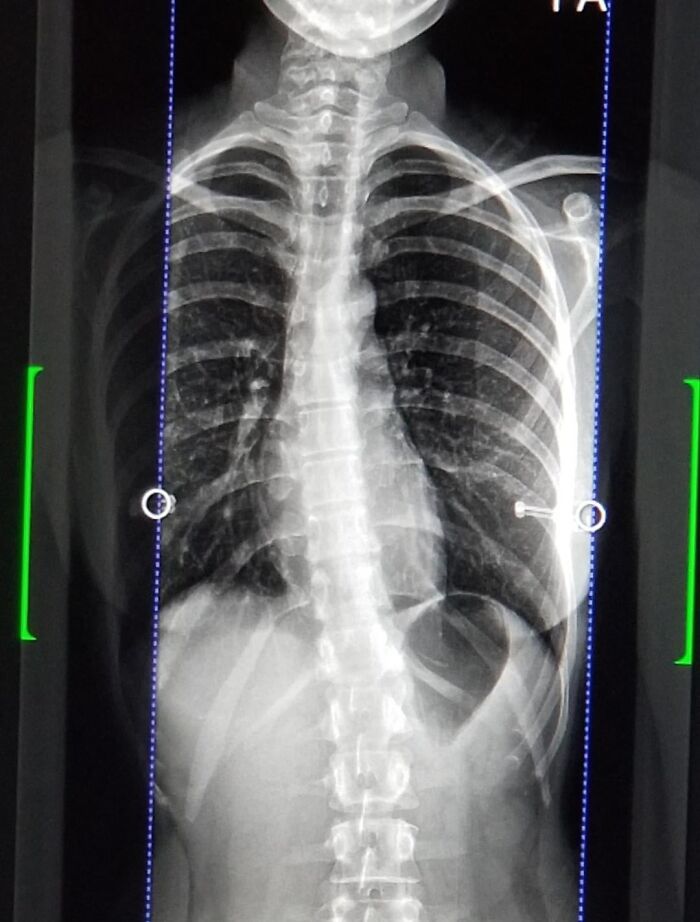

Update: Reddit Called My Scoliosis With My Ribs! Went And Got An Xray And The Doctor Confirmed. Ive Got Physiotherapy Tomorrow. Thanks Reddit :)

My ribs look exactly like that! I've had back issues my entire adult life.